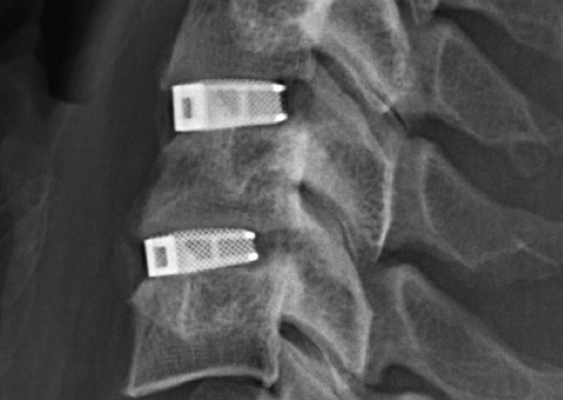

Кейджы межпозвоночных дисков поясничного отдела.

Межтеловой кейдж для фиксации позвонков

Чтобы операция дала наилучший результат, часто используется межтеловой кейдж, который должен отвечать таким требованиям:

- обеспечивать стабильность тел позвонков;

- гарантировать сохранение нормальной высоты межпозвоночных дисков, что позволяет избежать компрессии нервов;

- быть изготовленным со специальным пространством через которое, можно вводить костный цемент, искусственную костнозамещающую крошку или препаратов увеличивающих рост костной ткани ;

- Корригировать и фиксировать боковой (сагиттальный) и передний (фронтальный) баланс позвоночника;

- Удерживать нагрузку которая ложиться на ось позвоночника.

Безусловно, предельно качественное выполнение ТПФ обеспечивается при применении устройств 3-го поколения. Современные имплантируемые кейджи позволяют надежно зафиксировать патологически измененный сегмент позвоночника и устранить болевой синдром, обусловленный его остаточной подвижностью.